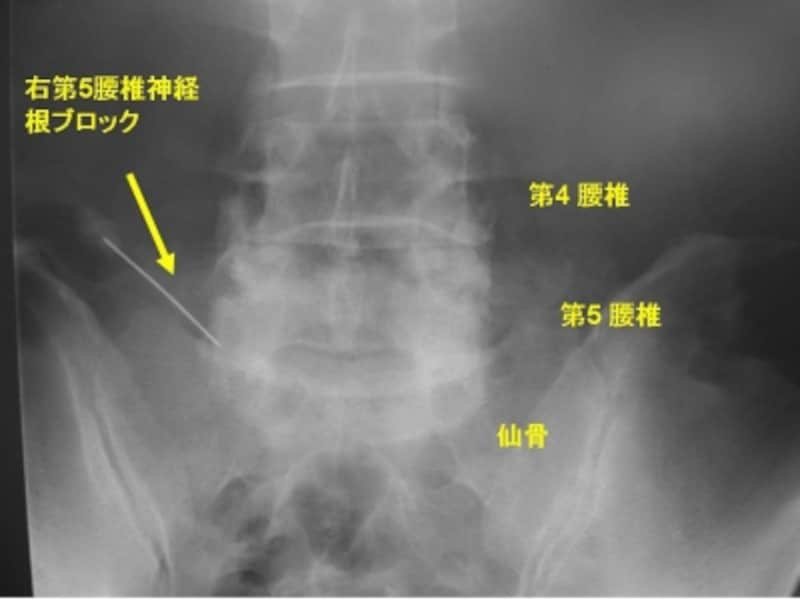

■神経根ブロック

狭窄されている神経に直接麻酔薬を注射します。この麻酔で一番主訴となっている症状が解消されていれば、手術の効果が期待できます。

右第5腰椎神経根ブロック

麻酔薬の注射後、腰痛、下肢痛、間欠性跛行は消失しました。効果の切れたその日の夜に、再度腰痛、下肢痛、間欠性跛行が再発しました。